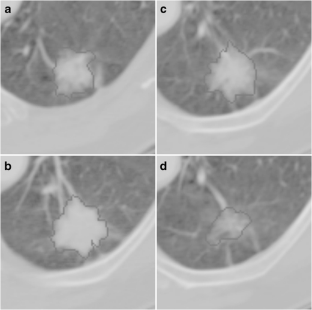

Fig. 2